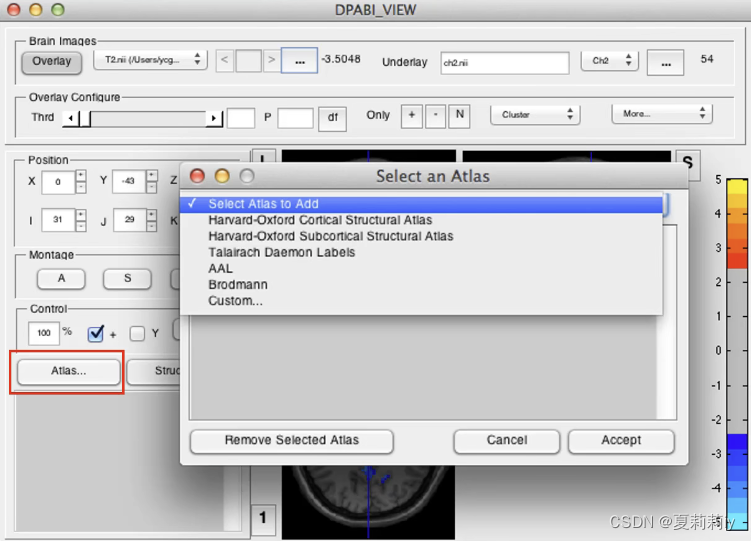

(5)Atlas:看点击的区域是在大脑的什么位置